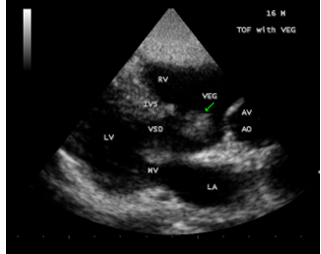

A 16-year-old cyanotic male was admitted with altered sensorium in the intensive care unit. He was diagnosed as Tetralogy of Fallot and advised corrective surgery earlier. He was afebrile and his pulse rate was 64 bpm and blood pressure 100/60 mmHg. He had headache, vomiting episodes and stiff neck for the past 3 days. Blood chemistry revealed normal. ECG and X-ray chest as in Figure 1 (boot-shaped heart) were consistent with Tetralogy of Fallot. Physical examination revealed uniform central cyanosis with clubbing, 2/6 systolic murmur in the left second intercostal space and a single second sound. Echocardiography revealed a non-restrictive, large, malaligned VSD (ventricular septal defect), biventricular aorta as shown in Figure 2. A large vegetation was attached to the crest of interventricular septum (IVS) as in Figures 3 and 4.

Figure 4: showing “the vegetation” (arrow) seen across the VSD (ventricular septal defect) in a 16 –year old boy with Tetralogy of Fallot.

The four components of TOF are ventricular septal defect (VSD), aortic override, right ventricular outflow tract obstruction and right ventricular hypertrophy. In unrepaired TOF, pathophysiology depends on the degree of RVOT obstruction. When obstruction of right ventricular outflow is mild to moderate and a fairly balanced shunt operates across VSD and the patient may not be cyanotic , called as “acyanotic” or “pink” tetralogy of Fallot. The patient may remain relatively asymptomatic until the balance between pulmonary and systemic circulation is disturbed. Echocardiography plays a key role in the diagnosis of infective endocarditis (IE) in TOF. Vegetation may occur on pulmonary and tricuspid valves [42] and a large vegetation occluding the VSD had been reported [43]. In this patient, a large vegetation attached to the crest of interventricular septum was shown in Figures 3 and 4.